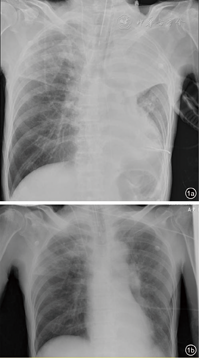

有研究试图确定使用这些气道廓清技术是否可以改善患者氧合、呼吸力学、肺功能,并减少机械通气时间、ICU住院时间、再入院或急诊次数、感染频率,提高生活质量等。一项儿科受试者的回顾性队列研究[96]评估了烧伤患者采用机械通气治疗时肝素和NAC的使用效果,结果表明,5000 U雾化肝素与3 ml 20% NAC交替使用,在最初的7 d内可减少小儿烧伤患者再次插管、呼吸机使用时间和死亡率。通过影像学变化也可判断治疗的效果,如气管镜吸痰治疗前后肺不张的改善情况(图1)。电阻抗断层成像(electrical impedance tomography,EIT)是以生物电阻为基础的功能成像技术,胸EIT借助微电压在胸内气体产生微电流,积分测算肺内气体随呼吸电阻值变化动态、立体成像,可以在气道廓清治疗过程中及前后比较治疗效果(图2)。

气道廓清主要包括患者评估、方案制定、方案执行和监测、回顾、记录4个步骤,每日应当对患者重新评估,以不断优化气道廓清方案(图3、图4)。患者评估需要包括患者基本病史、一般情况、功能评定(肺通气功能、咳嗽相关肌肉功能等)、需求评估(痰液黏度和量)和禁忌证评估等,机械通气患者还应当考虑患者呼吸支持水平、氧合情况、氧储备功能等。方案制定必须基于患者评估,同时建议包含痰液松动技术和咳嗽及相关技术以达到更好的痰液廓清效果,若痰液黏度较高,建议加强痰液水合或使用祛痰药物以促进痰液清除。